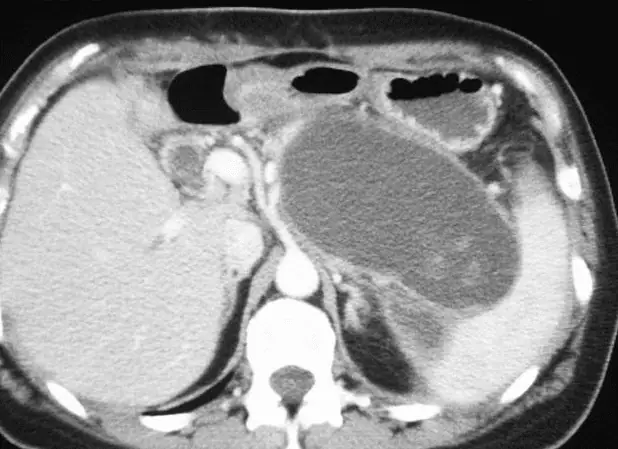

How many cases of the diagnostic depicted in the illustration involve the pancreatic head?

Explanation:

The head of the pancreas hosts around one-third of the pancreatic pseudocysts, while the tail hosts two-thirds of them. The most frequent causes in adults are alcohol and gallstone pancreatitis, whereas the most frequent cause in children is trauma .